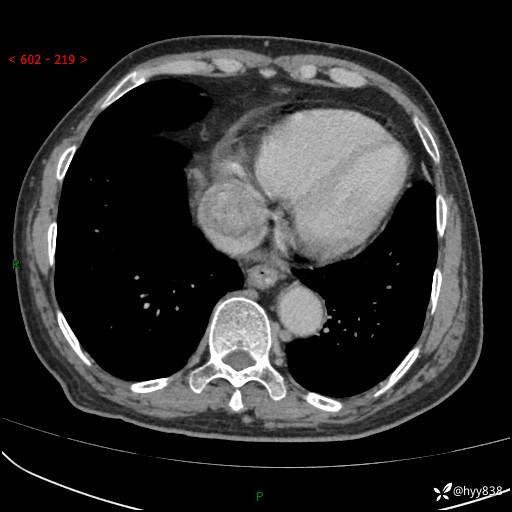

主诉:检查发现心脏肿物1周余。

现病史:患者一周余前因腹胀就诊我院消化科门诊,查心脏彩超提示右房内异常回声(粘液瘤?),无明显心慌、气喘、胸闷,无明显胸痛、咳嗽咳痰等不适,活动量增加后出现心慌、气喘不适。现为求进一步治疗,就诊我科,门诊遂以“心脏肿物”收入院。 自发病以来,精神睡眠一般,食欲尚可,大小便正常,体力下降,体重无明显变化。

胸部CT平扫+增强